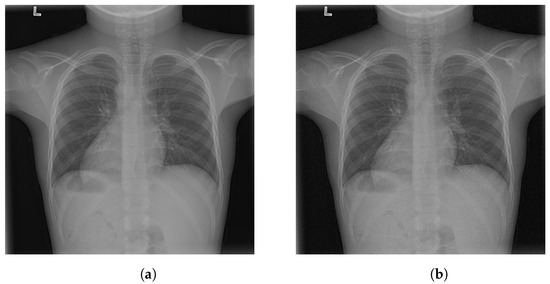

4.1. -LDP-Processed CXR Images

4.2. Qualitative Assessment of LDP-Processed CXR Images